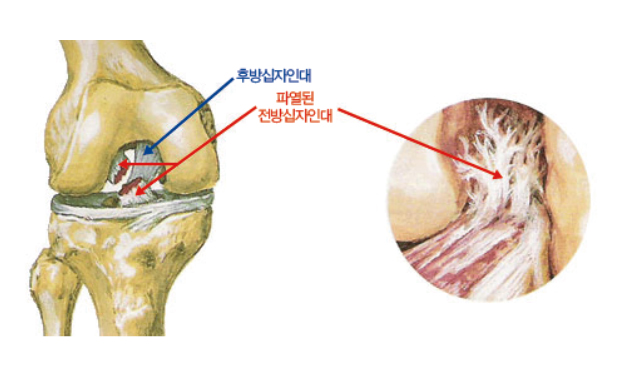

십자인대파열

십자인대란 무릎관절 내에 존재하는 인대로 전, 후방 2개로 구성, 모양이 X 모양으로 겹쳐있어 십자인대라 불리며

대퇴골에 대하여 경골이 전후방으로 이동되는 것을 방지하는 중요한 역할을 합니다.

이 중 전방 십자인대는 무릎관절 내에서 가장 흔하게 손상받는 인대로서 점프 후 착지와 같은 스포츠 손상으로 발생하는 경우가 많습니다.